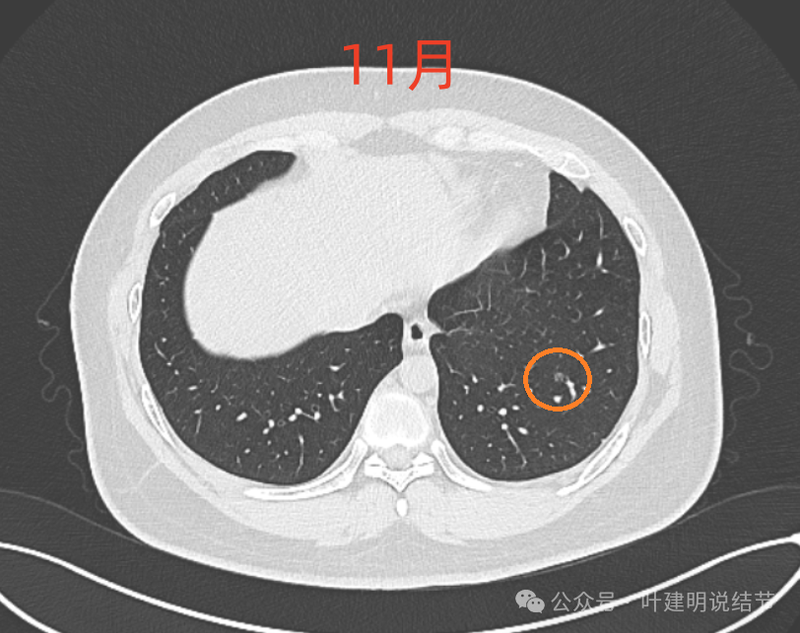

病灶4:

左下磨玻璃微小结节,轮廓与边界清楚,像是肿瘤范畴的,肺泡上皮增生或不典型增生可能性大,近期风险小。

8月时与后来的相仿。

这样的对比,似乎略有变化,又似乎说不上明显变化。本身扫描条件也可能不同。所以我常强调,不要在意过于细微的变化,因为这不影响临床决策。而影响到决策的变化一眼就看出来了。有些同道呀,喜欢拿放大镜看,然后告诉患者有进展,很危险,得尽快手术!只能呵呵了。下面是不同指南与共识对于随访的建议,大家可以自己看。

现在的人工智能辅助诊断系统太过敏感,非常微小的结节都给你找出来,但是对于临床来说并没有多大意义。当结节才几个毫米的时候,既没有办法明确到底是什么,也没有必要明确到底是什么,按照中华医学会肺癌诊疗指南,8毫米以下纯磨玻璃结节或5毫米以下实性结节(包括混合密度结节实性成分不足5毫米)也就是年度复查就可以。所以其实并不一定要在意到底有多少处结节,或者要考虑是什么。主要就关注最主要的病灶,如果主病灶仍没有风险可以年度体检复查,那就可以随访,不能也不必有过大的思想顾虑。我看了你的CT,目前这些结节均风险小,其中右侧桔色框起来的是所谓主病灶,仍是纯磨密度,又还小,考虑不典型增生可能性较大;左下桔色的也是磨玻璃密度,但轮廓不如右上这处清楚,若确实肿瘤范畴,也是原位癌或不典型增生可能性大,但也有少许慢性炎伴肺泡上皮增生或纤维增生的可能性;中叶绿色的密度过高,更符合良性些;右下黄色的过小,11月份的像磨玻璃密度,边界较清,但对比8月时的,此灶不太明显,当然本身过小,也可能没有扫到最明显层面,不过总归风险小,能观察随访(左下的也8月时更显淡和不明显点)。总体上,这几处病灶都是风险还低,可以继续半年到一年复查随访,真若有明显进展并具有一定的风险再来干预处理不影响预后。本身年纪轻,又是多发结节,目前的病灶又都风险低,可以过于积极赶紧处理。意见供参考!